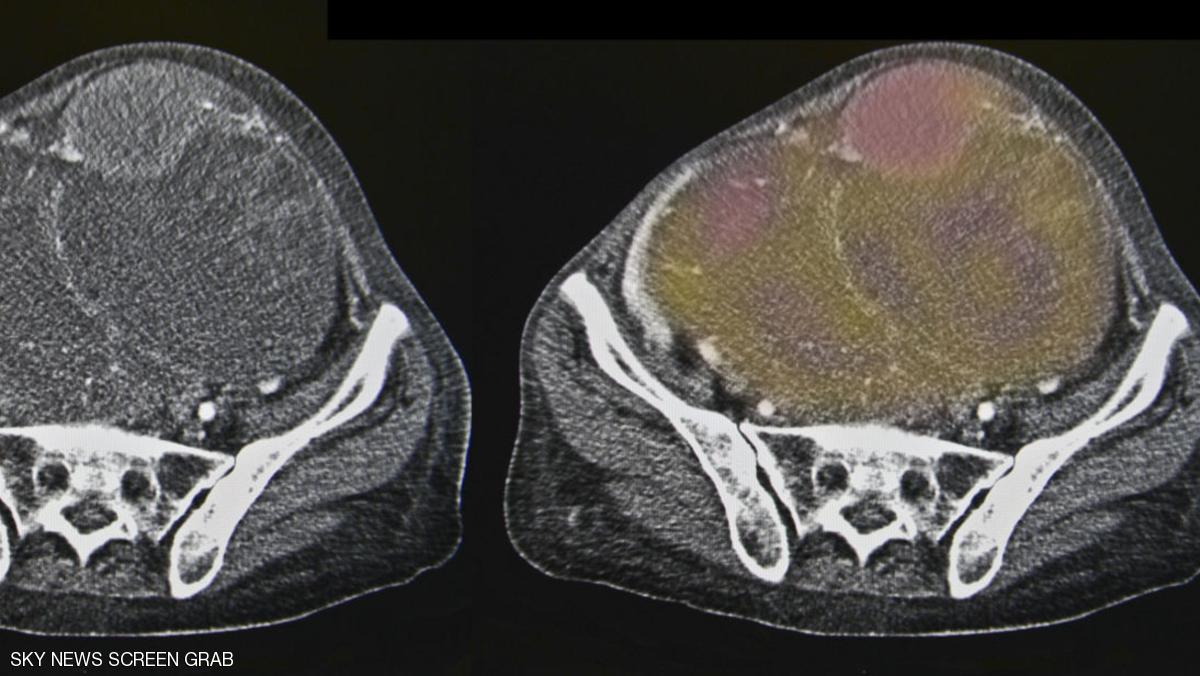

وخلال التجارب، استطاع عقار أونكس-0801 تقليص حجم الأورام في 7 من أصل 15 مريضا خضعوا للتجارب.